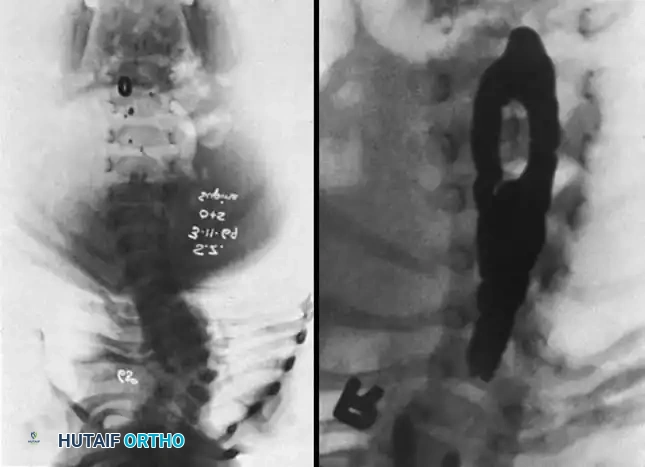

Image

Radiographic examples of progressive congenital curves requiring early intervention.